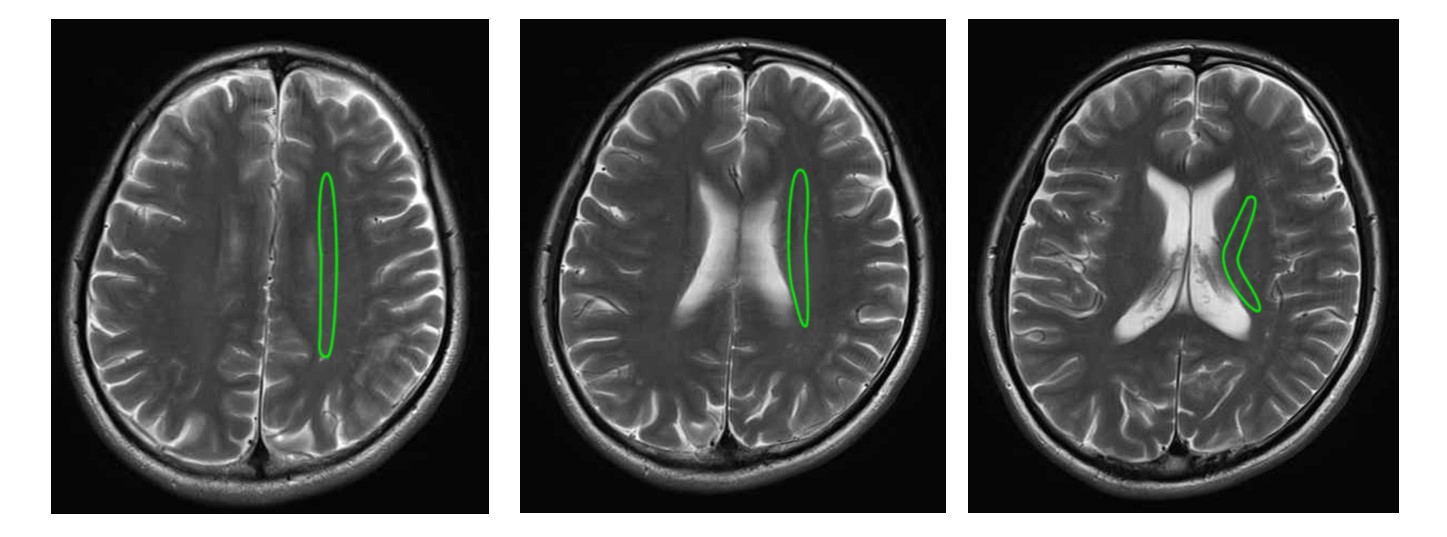

皮質脊髄路は内包後脚に収斂していきます。以下は放線冠のイメージ、内包周囲のMRIです。

放線冠MRI ↓↓↓

引用元:画像診断Cafe

内包周辺のMRI↓↓↓